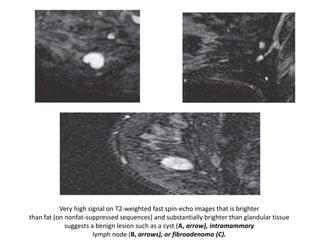

Very high signal on T2-weighted fast spin-echo images that is brighter

than fat (on nonfat-suppressed sequences) and substantially brighter than glandular tissue

suggests a benign lesion such as a cyst (A, arrow), intramammary

lymph node (B, arrows), or fibroadenoma (C).

Most malignancies,

unless frankly necrotic, have a signal intensity that is similar to that of

fibroglandular tissue